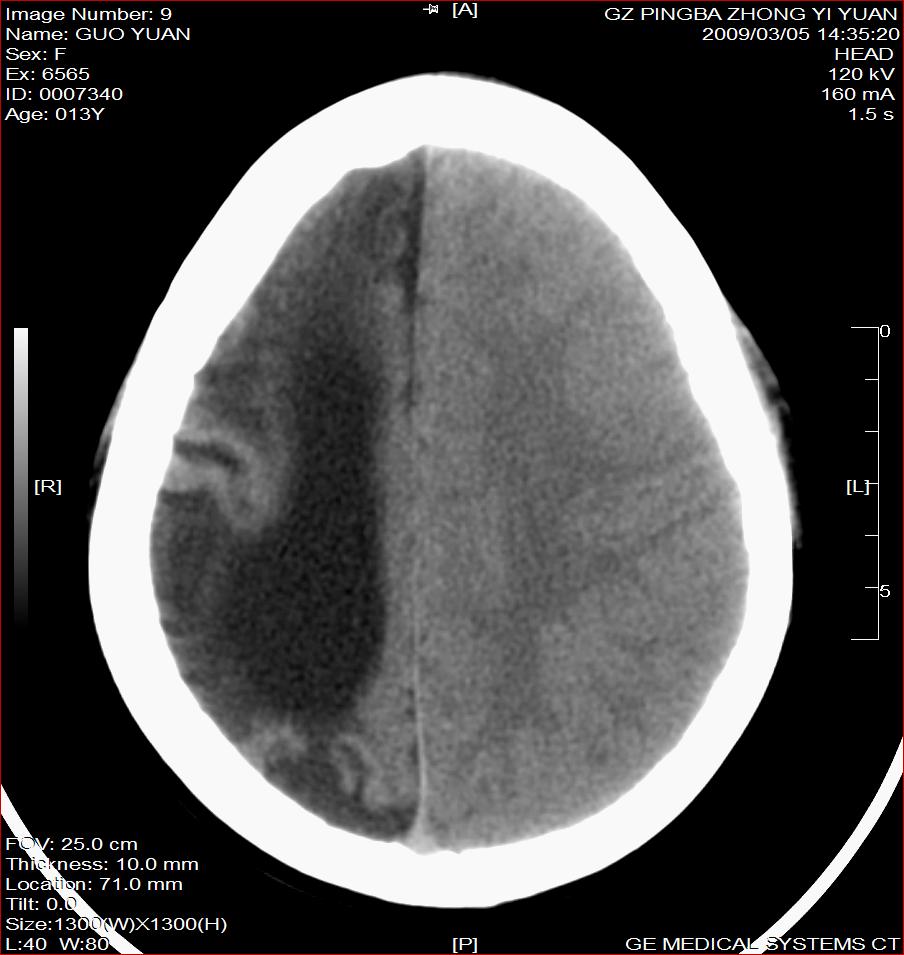

以下是引用杀毒软件在2009-3-6 17:32:00的发言:[br]右侧额颞顶部脑沟裂增宽,颞顶部楔形稍低密度影,侧脑室体部明显增宽,余脑实质内未见异常,中线结构居中。[br][br]考虑---右侧大脑半球发育不良并脑沟裂发育畸型可能性大

以下是引用随光逐影在2009-3-6 18:35:00的发言:[br]1)考虑右侧幕上半球发育不良并脑软化灶。2)双侧额部头皮软组织肿胀。